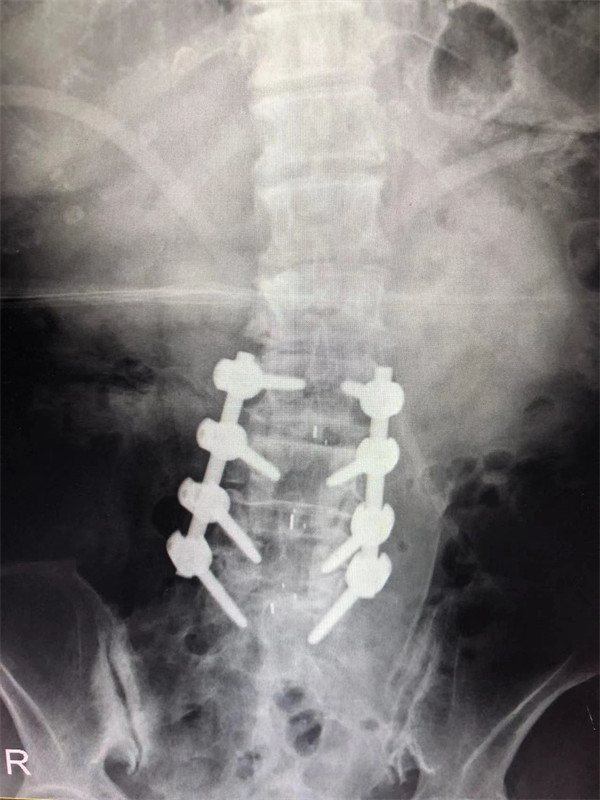

戈才華主任團(tuán)隊(duì)討論病情及手術(shù)風(fēng)險,并與麻醉科醫(yī)生多次討論術(shù)中麻醉風(fēng)險,經(jīng)過詳盡周密的布置之后,最終給阿婆在全麻下進(jìn)行腰3/4,4/5,腰5/骶1腰椎椎體間融合術(shù)。

術(shù)后阿婆腰痛伴雙下肢疼痛明顯緩解,術(shù)前疼得晚上睡不著覺的情況不再出現(xiàn)。阿婆和家屬連聲道謝,對醫(yī)生的治療技術(shù)和服務(wù)贊不絕口。

手術(shù)前↓

手術(shù)后↓